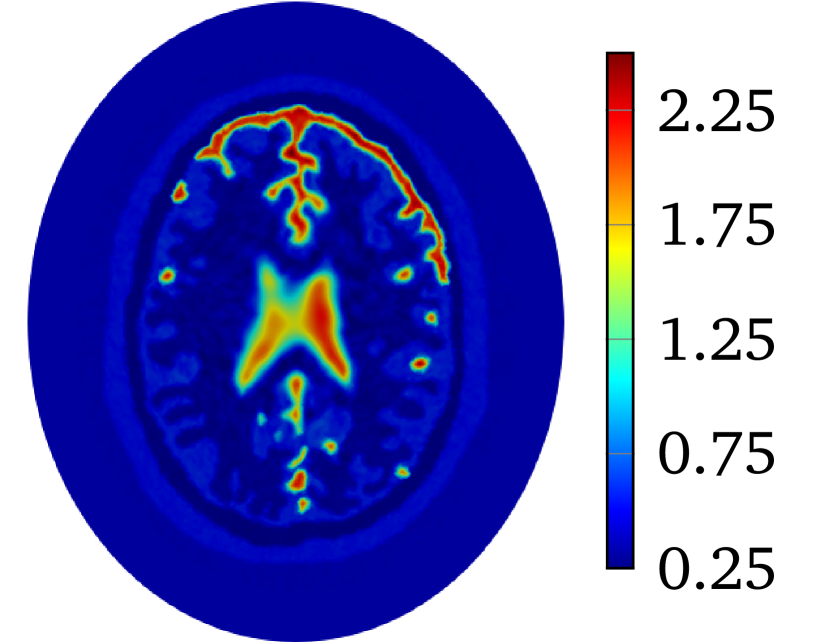

Though LM-SCEM performs well for reconstructing the conductivity map, its efficiency of the computation decreases quickly with the increase of measurements. Since EIT is not very sensitive to the change of interior conductivity, the electrical potential should converge faster than the convergence of the conductivity. The human-brain model is used here for numerical experiments with LM-SCEM. The elliptic domain is characterized with 8 cmtimes8cm8\text{\,}\mathrm{c}\mathrm{m} major and 9 cmtimes9cm9\text{\,}\mathrm{c}\mathrm{m} minor axes, and the domain is meshed with 36893 triangular elements. The parameters are given as α0=150subscript𝛼0150\alpha_{0}=150, a=2.0𝑎2.0a=2.0 and β=1×103𝛽1E-3\beta=$1\text{\times}{10}^{-3}$. The current patterns I(2)superscript𝐼2I^{(2)} and I(3)superscript𝐼3I^{(3)} are used in the reconstruction. With 60 dBtimes60dB60\text{\,}\mathrm{d}\mathrm{B} noise, the iteration is terminated when τL2<1×104subscriptnorm𝜏superscript𝐿21E-4\|\tau\|_{L^{2}}<$1\text{\times}{10}^{-4}$ or the maximum number of iterations equals 30. The reconstruction based on LM-SCEM is shown in Figure 7(a). 𝒰superscript𝒰\mathbfcal{U}^{k} of each current pattern is computed with SCEM and σksubscript𝜎𝑘\sigma_{k} for k𝑘k-th iteration, ηbsuperscript𝜂𝑏\eta^{b} easily follows then. The variation of the relative error η𝜂\eta and ηbsuperscript𝜂𝑏\eta^{b} are shown in Figure 6(a) and Figure 6(b), respectively. As can be seen, η𝜂\eta slowly converges to 4.09%percent4.094.09\%. This error is much larger than the input noise level, this is mainly caused by the complexity of the phantom and the high contrast of σ𝜎\sigma among different tissues. But the potentials on the boundary for both I(2)superscript𝐼2I^{(2)} and I(3)superscript𝐼3I^{(3)} converge fast to a level of ηb<1×104superscript𝜂𝑏1E-4\eta^{b}<$1\text{\times}{10}^{-4}$ in few iterations. Therefore, the boundary potential converges much faster. This property is exploited here to accelerate the computation by mixing LM-SCEM and LM-DCM, as demonstrated in Algorithm 2. In this computation, the LM-SCEM is stoped when ηbsuperscript𝜂𝑏\eta^{b} for all current patterns are smaller than 1×1031E-31\text{\times}{10}^{-3}. The LM-DCM is performed in the region Ω={x|xΩ,dist(x,Ω)>5 mm}superscriptΩconditional-set𝑥formulae-sequence𝑥Ω𝑑𝑖𝑠𝑡𝑥Ωtimes5mm\Omega^{\prime}=\{x\ |\ x\in\Omega,\ dist(x,\partial\Omega)>$5\text{\,}\mathrm{m}\mathrm{m}$\} with δd=5 mmsubscript𝛿𝑑times5mm\delta_{d}=$5\text{\,}\mathrm{m}\mathrm{m}$. The potential on ΩsuperscriptΩ\partial\Omega^{\prime} is computed with SCEM and the reconstructed σ𝜎\sigma from LM-SCEM. The power density in ΩsuperscriptΩ\Omega^{\prime} can be reconstructed with the method introduced by Ammari et al [4]. However, it requires the knowledge on the deformation caused by the ultrasonic waves, therefore, we compute it with DCM instead. Noise with SNR=60 dBabsenttimes60dB=$60\text{\,}\mathrm{d}\mathrm{B}$ is added, and LM-DCM is used for the reconstruction. The relative error η𝜂\eta is given in Figure 6(a). The conductivity map is reconstructed with η=8.13×104𝜂8.13E-4\eta=$8.13\text{\times}{10}^{-4}$ in 30 iterations, and the result is given in Figure 7(b). Here, the time required for 30 LM-DCM iterations is about 20 minutes which is approximately the time needed for one LM-SCEM iteration. So the reconstruction efficiency is greatly improved, and better results are obtained. A similar computation with 40 dBtimes40dB40\text{\,}\mathrm{d}\mathrm{B} noise is further considered here. As seen in Figure 6(b), increasing noise does not influence much the convergence of the boundary potential, therefore, this mixed approach can be a good way to remove noise from the measured power density. With 40dB noise in the reconstructed power density in ΩsuperscriptΩ\Omega^{\prime}, the distribution of σ𝜎\sigma obtained with LM-DCM is shown in Figure 7(d). Comparing it to the results obtained with LM-SCEM, as shown in Figure 7(c), a better noise tolerance is observed in LM-DCM.

Refer to caption

(a) LM-SCEM, SNR = 60 dBtimes60dB60\text{\,}\mathrm{d}\mathrm{B}

(b) Mixed, SNR = 60 dBtimes60dB60\text{\,}\mathrm{d}\mathrm{B}

(c) LM-SCEM, SNR = 40 dBtimes40dB40\text{\,}\mathrm{d}\mathrm{B}

(d) Mixed, SNR = 40 dBtimes40dB40\text{\,}\mathrm{d}\mathrm{B}

Figure 7: The conductivity map of human-brain model reconstructed with current pattern I(2)superscript𝐼2I^{(2)} and I(3)superscript𝐼3I^{(3)}. The reconstruction with only LM-SCEM are given in (a) and (c) for 60 dBtimes60dB60\text{\,}\mathrm{d}\mathrm{B} and 40 dBtimes40dB40\text{\,}\mathrm{d}\mathrm{B} noises. Corresponding reconstructions by mixing LM-SCEM and LM-DCM are given in (b) and (d).